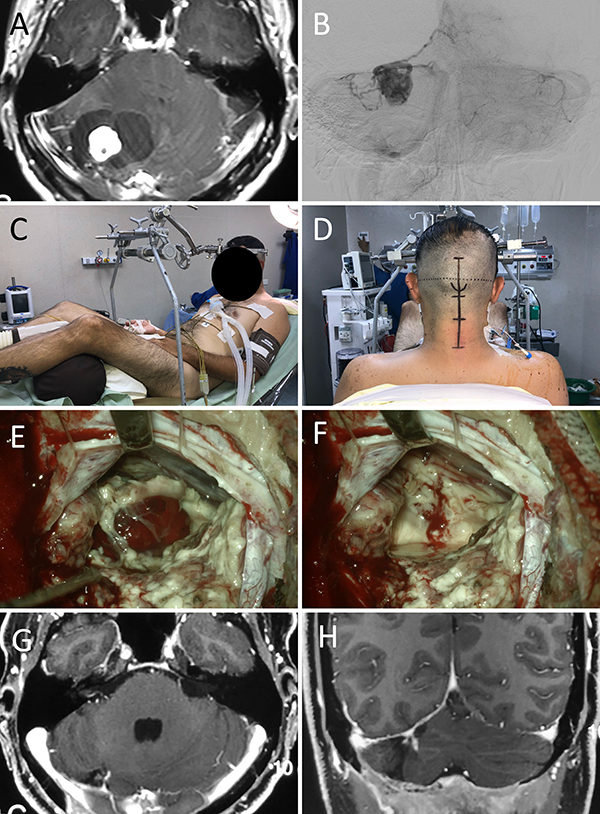

Figura 9: Hemangioblastoma de fosa posterior A: RM preoperatoria; B: Angiografía digital preoperatoria; C-D: Posición; E-F: Hallazgos intraoperatorios.